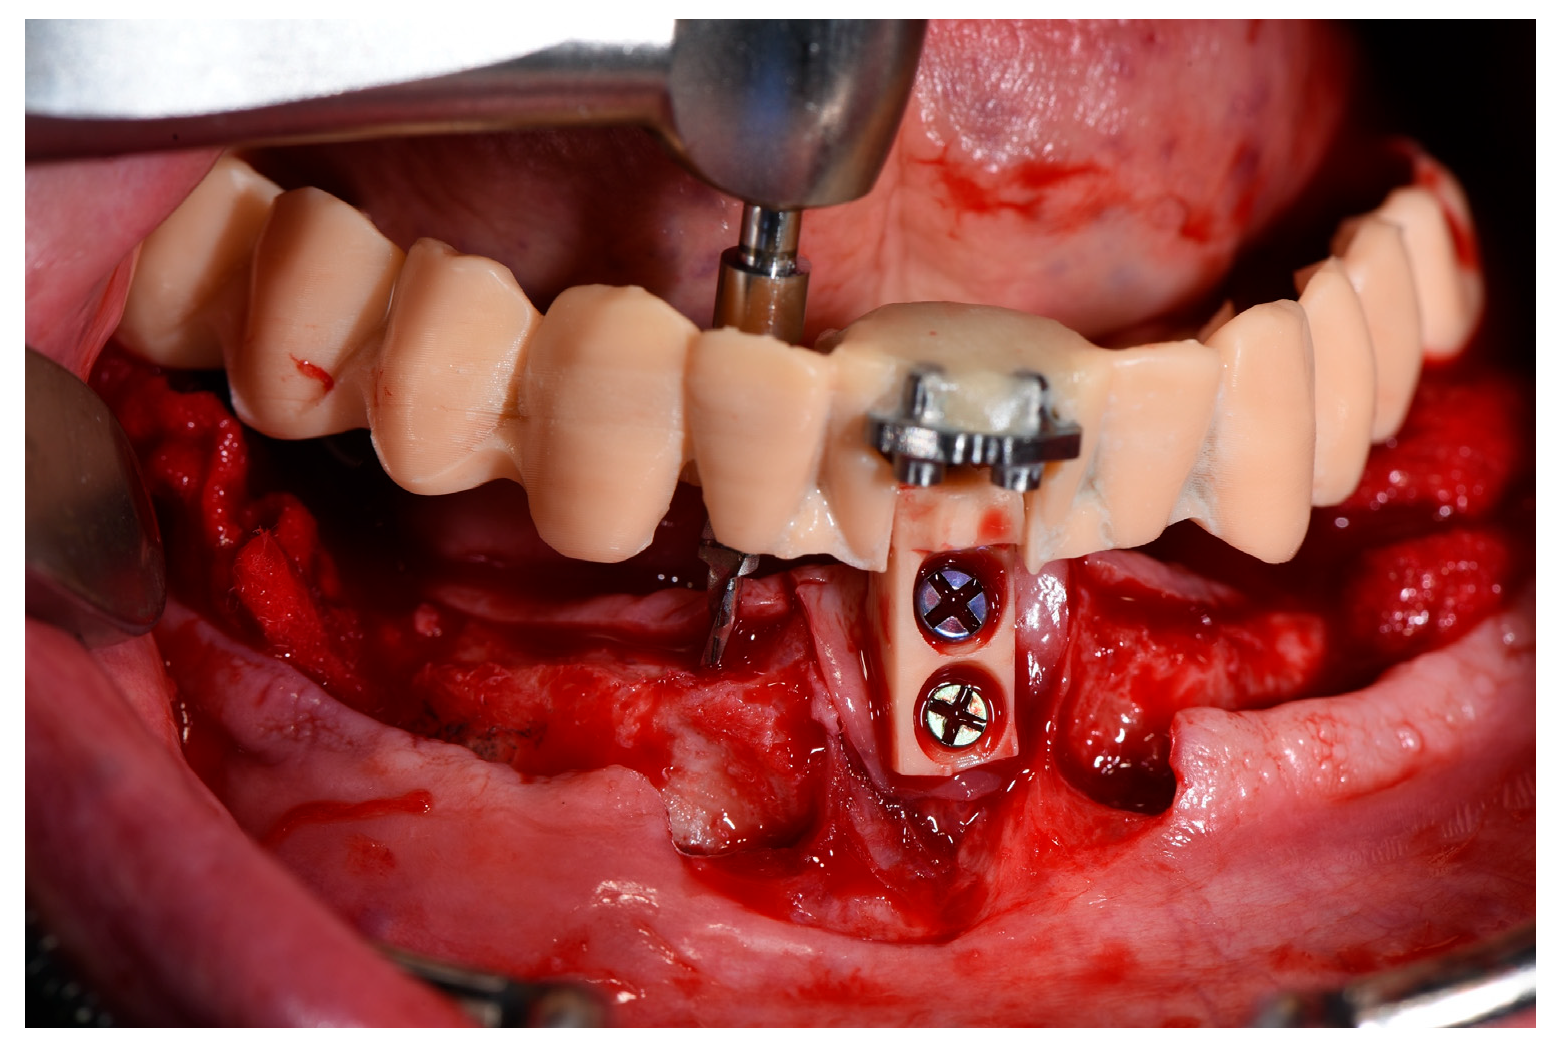

2.3. Surgical Procedure